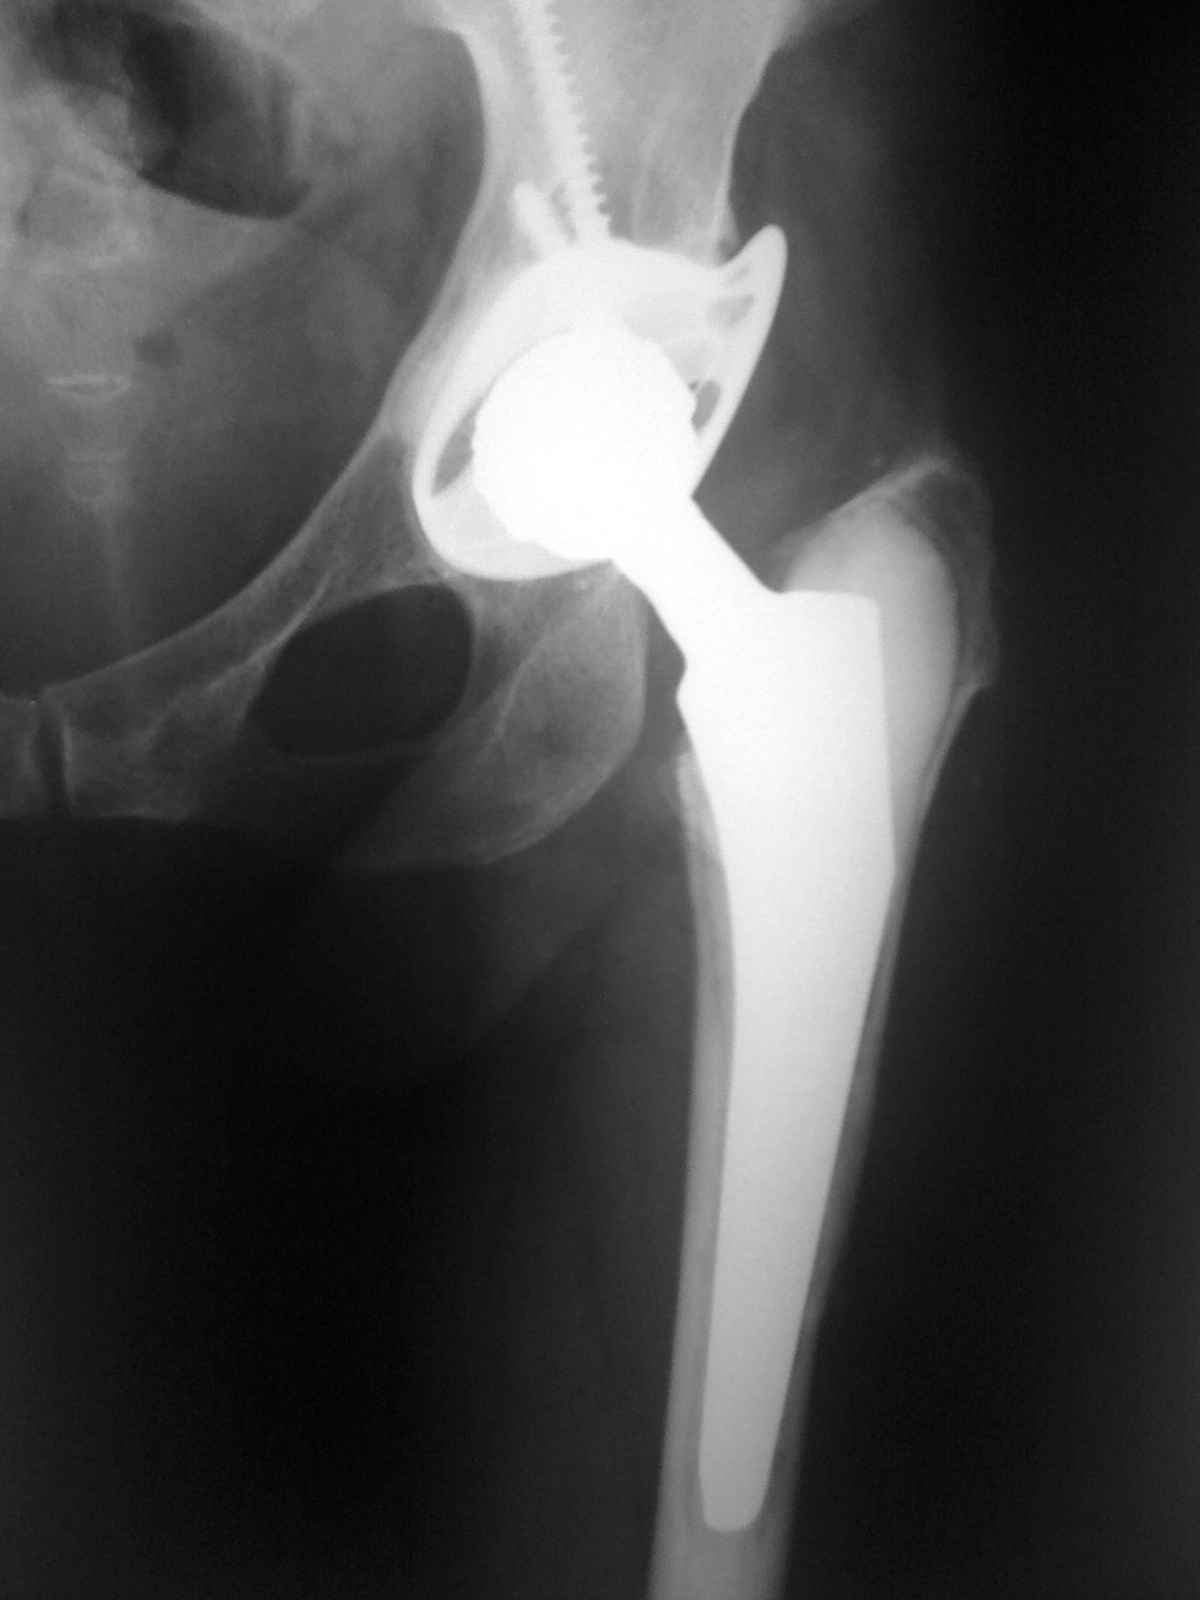

12 лет назад пациентке по поводу ревматоидного полиартрита выполнено ТПТС. Проблем не было.

7 дней назад в покое без видимых причин возникла резкая боль в паховой области. Боль постепенно усиливалась и к вчерашнему вечеру стала нетерпимой. Обратилась к хирургами по месту жительства. Заподозрено ущемление бедренной грыжи. Взята в эстренном порядке в операционную. На операции выявлена напряженная гематома со сгустками идущая из области вертлужной впадины. источник кровотечения не выявлен. Гематома эвакуирована, задренирована.Вопрос. Причина? Тактика дальнейшего ведения?

Уважаемый Сергей! Желательно увидеть рентгенограммы этого сустава, не исключен "конфликт" костной ткани и конструкции. Возможно,после рентгенографии многое поймете сами.

Наиболее вероятная причина - это псевдоопухоль (а там пара металл-металл) с появлением крови, либо - учитывая ревматоидную природу артроза - травматизация гипераплазированной синовиальной с образованием гематомы.

Отсюда и лечение - на всякий случай - ангиография, при отсутствии признаков повреждения сосудов - ревизия с иссечением синовии и заменой вкладыша.